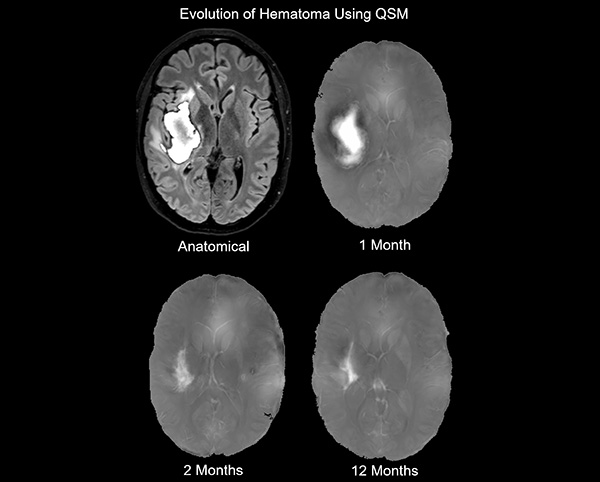

QSM Hematoma Image

Quantitative Susceptibility Mapping allows for quantitative volumetrics of hematoma in patients with intracerebral hemorrhage

Evolution of Hematoma